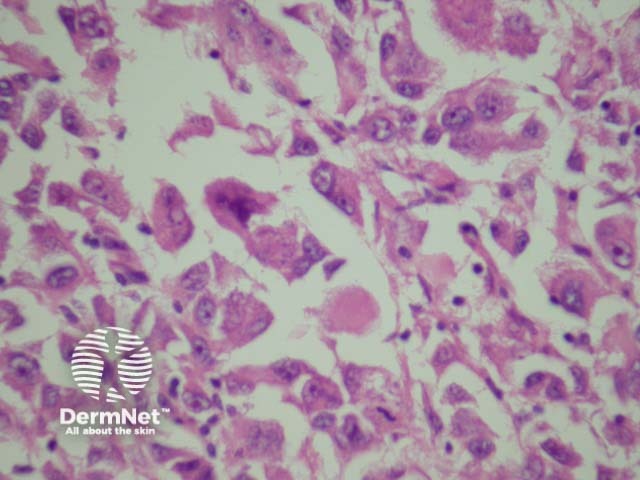

Rhabdoid melanoma |

Presence of large epithelioid cells with abundant cytoplasm containing a round eosinophilic inclusion (figure 29). |